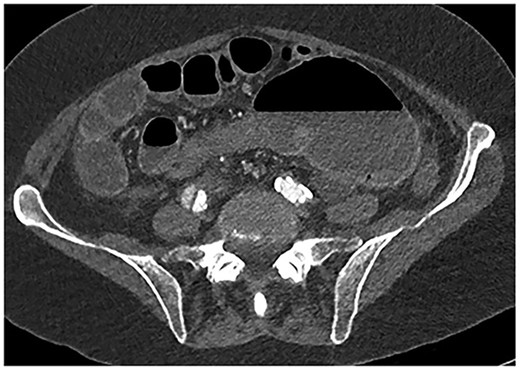

A 61-year-old female with known Marfan Syndrome was admitted to the emergency department with 3-day history of abdominal pain, nausea, vomiting and bowels not opening. Past medical history included three previous episodes of Type A aortic dissection, recent aortic root and ascending aorta replacement alongside bioprosthetic aortic valve replacement. She was an ex-smoker and usually independent at home. On presentation, the patient was haemodynamically stable and apyrexial. Biochemical results were unremarkable except for a Lactate dehydrogenase (LDH) of 309 and a C-reactive protein (CRP) of 101. On examination, she had a diffusely tender and distended abdomen, without signs of peritonism. An erect chest X-ray shows left pleural effusion with a dilated aortic root (Fig. 1). A computed tomography (CT) of thorax, abdomen and pelvis was requested, which demonstrated a caecal volvulus with a dilated cecum of 8.8 cm and upstream small bowel dilatation with air fluid levels, and a chronic aortic dissection extending from the ascending thoracic aorta to the common iliac (Figs 2–4). Following consultation between radiologists, cardiothoracic surgeons and general surgeons, she underwent an emergency laparotomy and right hemicolectomy with side-to-side ileocolic anastomosis. Intraoperatively, the caecal volvulus, comprising a dilated ascending colon measuring up to 10 cm, was delivered and resected along with its mesentery. The patient was admitted to the intensive care unit post-operatively for close blood pressure monitoring and control and stepped down to level 3 wards on day-2 post-operation. Her operation was complicated by a small infected wound haematoma thatwas managed with a 5-day course of ciprofloxacin. A CT of the abdomen and pelvis to investigate a rising CRP on day-9 revealed a subcapsular liver haematoma thath was managed conservatively. The patient was discharged 12-days post-operatively. Histology from the resected colon showed evidence of ischaemia in keeping with a closed loop obstruction such as caecal volvulus. There was also an incidental T1 N0 colonic tumour arising from a sessile serrated polyp and two other serrated polyps. A colonoscopy to inspect the remaining colon has been arranged.

CT abdomen axial view demonstrating the Beaking sign—a progressive tapering of afferent and efferent limbs leading into the twist.

Fluid-filled mid to distal appendix with some gas in the proximal part outlined with yellow arrows. Appendix is seen within the upper abdomen, indicating an increased likelihood of caecal volvulus.